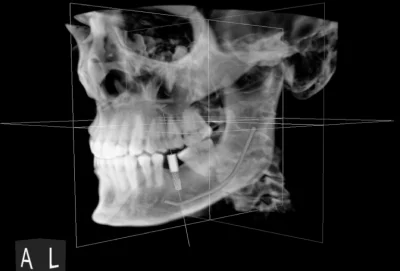

CBCT

Explore CBCT imaging at My Harmony Smiles. This detailed 3D scanning helps us plan your dental care with better accuracy.